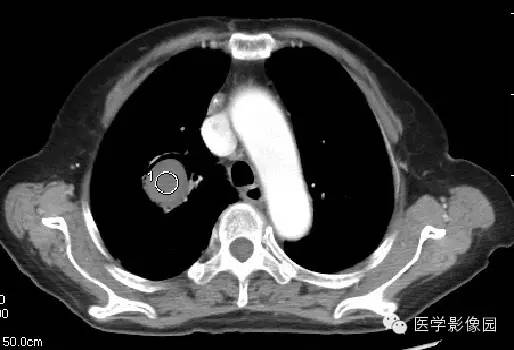

CT表现

右肺内见一圆形空洞病灶,内有圆形曲菌球,边缘光滑,可随体位改变而变动,曲菌球与洞壁之间可见“新月征”。

影像表现为肺内空洞病灶内有圆形软组织密度影,改变体位后曲菌球位置可变动,曲菌球与洞壁见出现一新月形间隙,称为“新月征”。